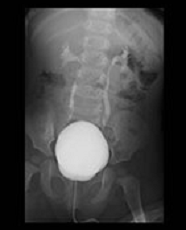

主に子宮卵管造影(HSG:Hysterosalpingography)を行っています。子宮や卵管〜卵管采までの経路を造影して撮影します。主に不妊の原因を調べる検査です。